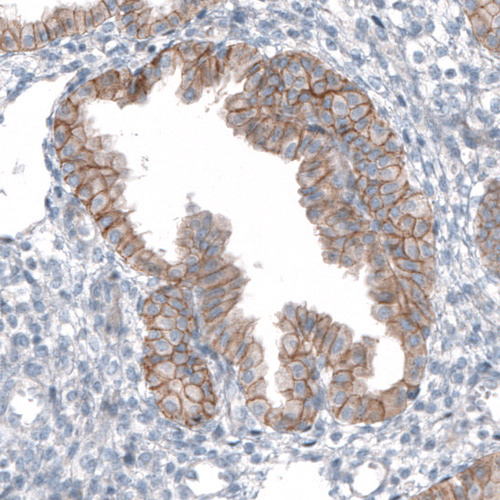

Immunohistochemical staining of human endometrium shows moderate to strong membranous positivity in glandular cells.